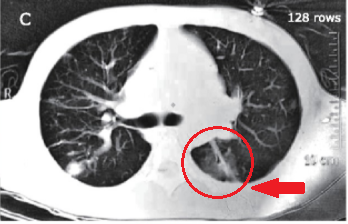

(第二次胸部CT)

直到2018年,患者去了一家省级三甲医院,医生看完情况后也觉得很奇怪,于是安排重新做了一次胸部增强CT,并且做了三维重建。

这次胸部CT增强扫描,发现在患者的左侧胸腔里面有一条线性阴影,而且还挺长的。做了三维重建,的确是有一根细长的东西在肺里面,这不简单啊。

(第三次胸部CT)

但回顾患者以前的胸部CT,应该是一开始就有的,只不过之前它周围病灶太多,看不清晰,现在病灶少了一些,而且还做了三维重建,看起来就清晰一些了,能认出是一根细长的阴影,这肯定不是患者体内原本就有的,也不会是普通的感染痕迹,从来没有见过细菌或者病毒造成的感染能如此规整(一条直线型)。

问题是,肺里面为什么会有这个细长型的阴影呢,看起来像是一根牙签啊,一根大号牙签,比如说烧烤店里面那些羊肉串、牛肉串的竹签?

由于竹签本身不容易在CT上显影,因为密度不够高,如果是铁签,一开始就会发现了。现在之所以能发现竹签的踪影,应该是竹签周围有一圈炎症,炎症显影了,带着竹签的痕迹显出来(备注:请放射科的老师指正)